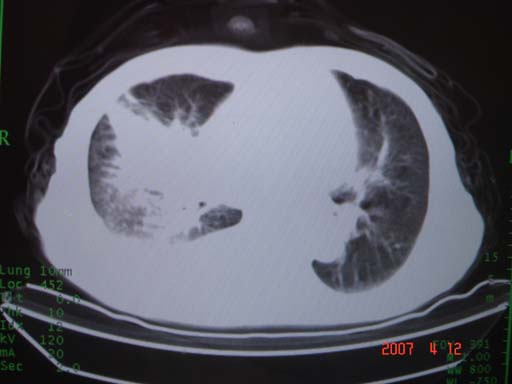

帮我 看看。男77岁咳嗽咯血2月发热2周!病人一般情况可 口痰为鲜红,有点象洗肉水(我看见他吐的痰了)

病灶局限在右肺中上叶,呈大片状实变影,内见空气支气管征,支气管分支较柔软,纵隔内未见肿大淋巴结.支持:感染性病变_1 大叶性肺炎.2 干酪性肺炎.

优先考虑右上肺干酪性肺炎并同侧中叶播散、胸腔积液。分析:右膈肌未见升高、纵隔未见明显右移,胸部各组淋巴结未见可疑肿大,中叶可见支气管铸形,肺野、肺门未见可确定肿块。

年龄偏大,应考虑右肺中央型肺癌并阻塞性肺炎 阻塞性肺不张,胸腔积液

考虑右侧中心型肺癌伴中叶肺不张,右侧 胸腔积液

右肺上叶中心型肺癌并上叶阻塞性肺炎,中叶炎症,右侧胸腔积液

右肺上叶后段支气管中断,首先考虑中央型肺癌并右肺不张及纵隔淋巴结转移,右侧胸腔积液。

有点象洗肉水的痰,其来源应当是实变引起的血细胞渗出导致,可见支气管气象,实变区有虫蚀状空洞,有明显胸腔积液,未见明显肺门区肿块影,考虑继发型肺结核,干酪性肺炎

右肺上叶实变,实变范围如此之大,如果用肺癌解释的化,应该是比较大的支气管开口发生完全阻塞,但观察上叶前后段支气管还是比较通畅,所以应考虑感染性病变,大叶性肺炎可能,建议抗炎治疗后复查。

考虑右中上叶大叶性肺炎,右侧胸水。抗炎治疗后复查。